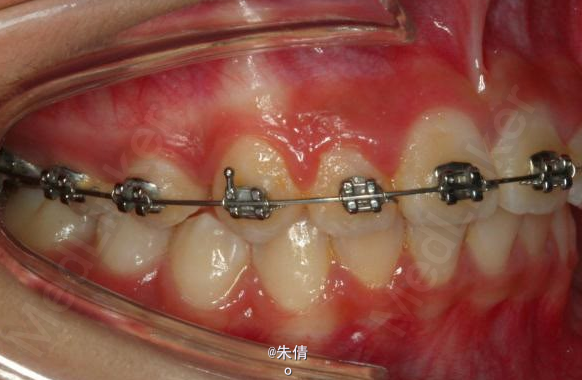

对于面型较好,拥挤度不大的病例,推磨牙向后不失为一种很好的方法,当然现在推磨牙后向的手段和方法很多,但是主要 是适应证的问题。我认为我们在做推磨牙向后,首先是考虑拥挤度,第二个要考虑的是现有的面型,第三点也是很重要的一点,是考虑牙弓后段拥挤度,Tweed-Merryfireld拥挤度的诊断方法将牙弓拥挤度分析分为三段,牙弓前段拥挤度,牙弓中段的拥挤度,以及牙弓后段的拥挤度。不管用什么方法或是手段推磨牙向后,一定不能将牙弓前端矛盾移到牙弓中段或是后段。今天给大家看一直面型,拥挤度不是很大推磨牙向后的病例。希望对大家能有所帮助。